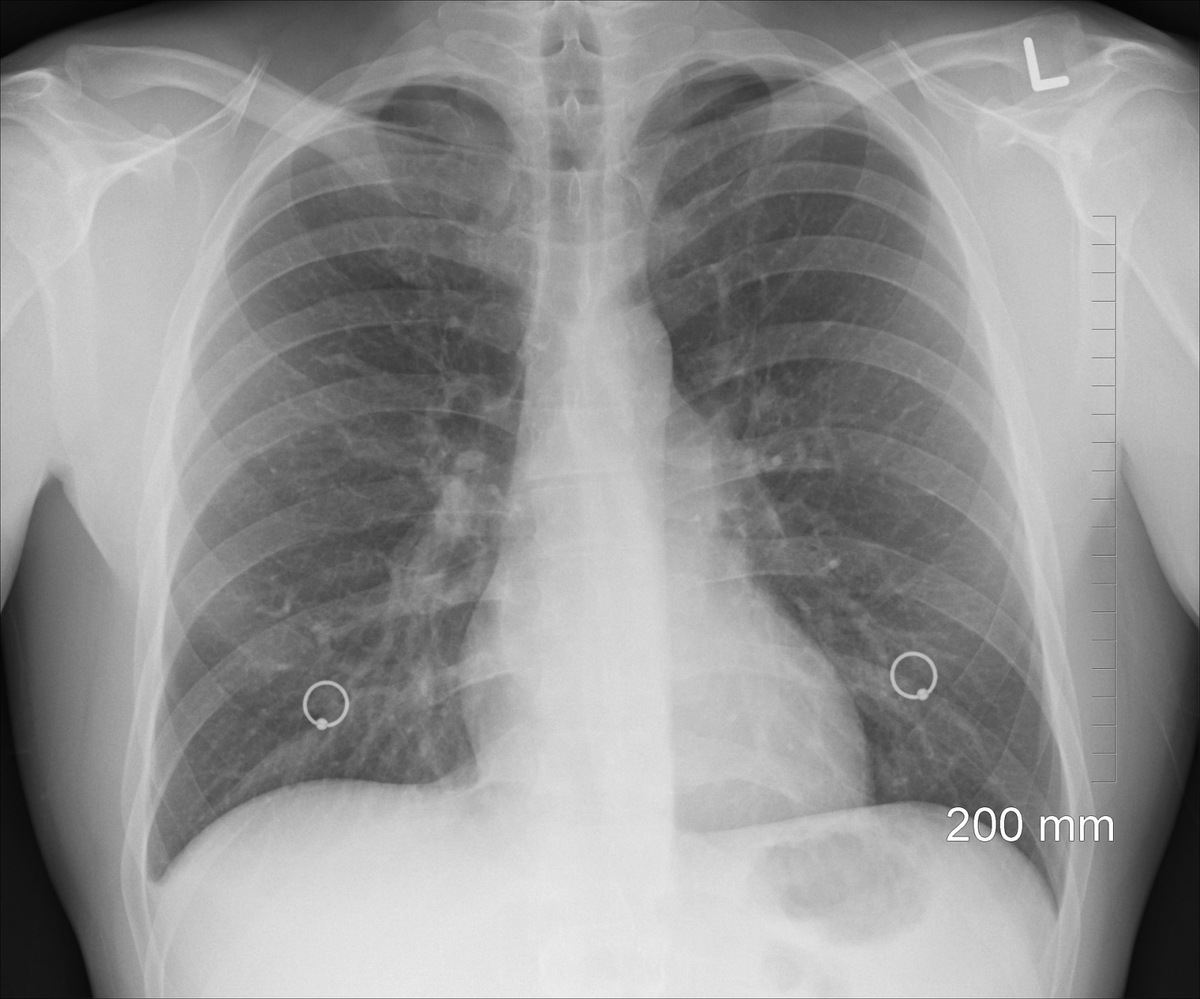

I'm not talking about the coronavirus. Because of this, you cough until you feel like coughing up your lungs, as they say. I'm talking about a ruptured lung. Technically, this is called a spontaneous pneumothorax, which means that one of the lungs, in the worst case scenario both of them, suddenly simply bursts. That happened to my friend. But she didn't find out until three days later... until then, she'd dealt with it normally, thinking she had the common cold that was accompanied by a brutal cough. When she wasn't able to walk up the stairs to the first floor after those three days, she went to the doctor. She wanted to dismiss her with some medicine, but thank God the patient stood her ground and literally forced the doctor to do a lung X-ray. And lo and behold. There it was! The lung deflated like a balloon after a crazy party.

Rentgen plic.

Rentgen plic.Source: pixabay.com/oracast